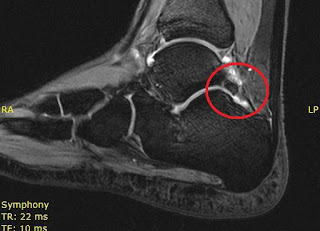

I hope anyone who is dealing with os trigonum or FHL tendon

issues, or just injuries and recovery in general, has found this blog helpful.